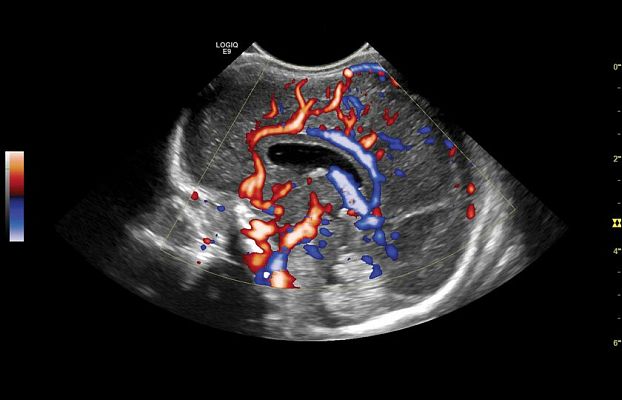

Клинические изображения

- B-Flow и Color B-Flow — технология прямой недопплеровской визуализации кровотока в режиме реального времени, которая позволяет получить гемодинамический профиль с повышенной чувствительностью и разрешением без нежелательных сигналов от окружающих тканей в сосудах всех типов, от крупных, например, сонной артерии, до мелких, например, сосудах паренхиматозных органов.

- Контрастно усиленный ультразвук (CEUS) — использование контрастных препаратов для повышения чувствительности при визуализации кровотока в сосудах.